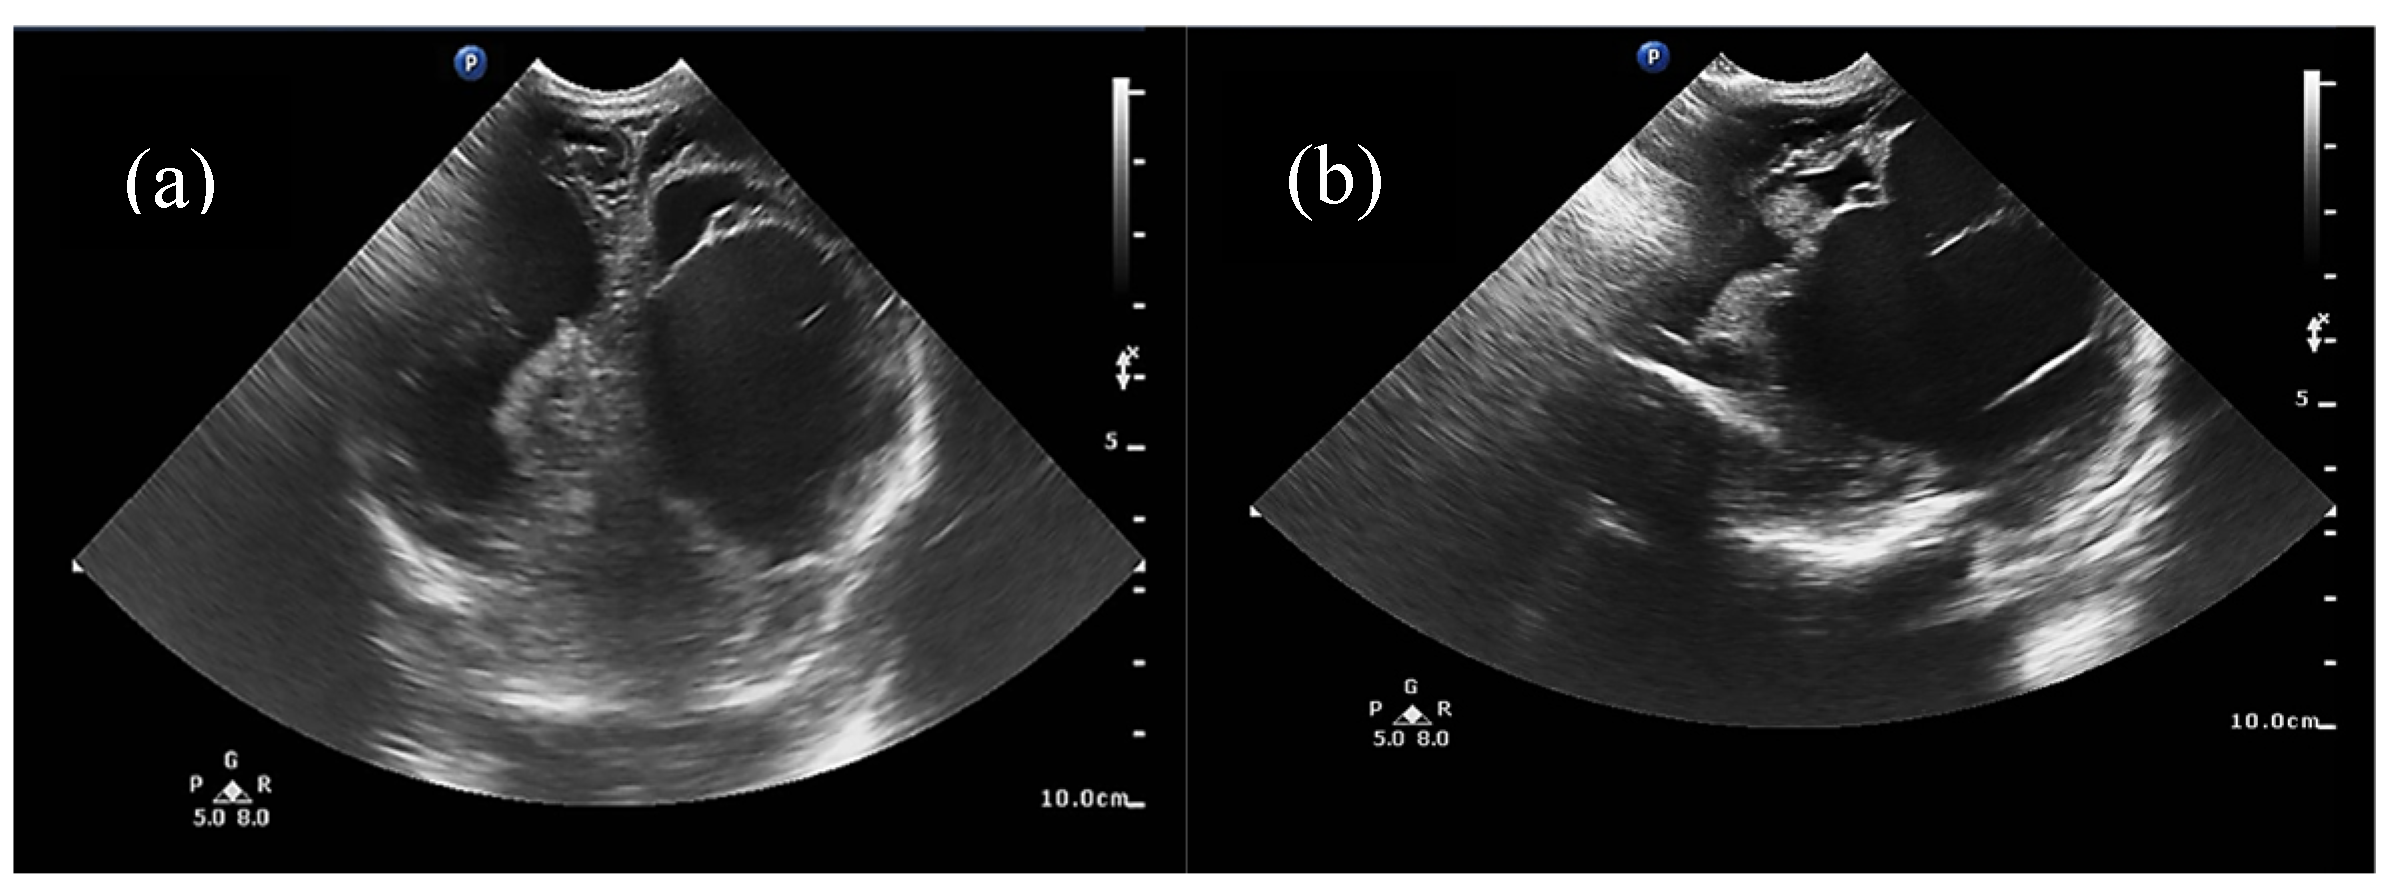

For some patients, the diagnosis was completed by brain MRI cerebral angio-CT (with iodinated radiocontrast agent at a concentration of 300 mg I/mL) methods for a better understanding of the Galen vein aneurysm morphology and its anatomical relations (see Figure 3, Figure 4, Figure 5 and Figure 6). Three of five patients who performed superior imaging techniques had large varieties of the Galen vein malformation, with variable degrees of compressive effect and secondary changes in the appearance of the midline and ventricular symmetry. Three patients presented with corpus callosum dysgenesis and three others with engorged arteries of the Willis polygon and enlarged pericerebral venous sinuses. None of the patients underwent an angiographic study of the arteriovenous malformation they had been diagnosed with in order to conceivably facilitate the perspectives of endovascular embolization in a center with expertise.

Figure 4. Angio-MRI sequence: Vascular aneurysmal dilation located at the level of the quadrigeminal tank (blue arrow), communicating with the large cerebral veins and the left middle cerebral artery, with collaterals emerging from the choroidal and posterior cerebral arteries—highly suggestive aspect of Galen vein aneurysm.

Figure 5. Three-dimensional reconstruction angio-MRI: (a) Sagittal view of the VoGM, (b) posteroanterior view in coronal plane. Aneurysmal median prosecephalic vein drained by the right sinus (blue arrows). Transverse/sigmoid sinuses and internal jugular veins of increased caliber (pink arrows). Multiple vascular pathways at the level of the basal nuclei connecting the anterior and posterior circulation. Carotid, vertebral arteries and basilar trunk exerting mass effect on the bulb.